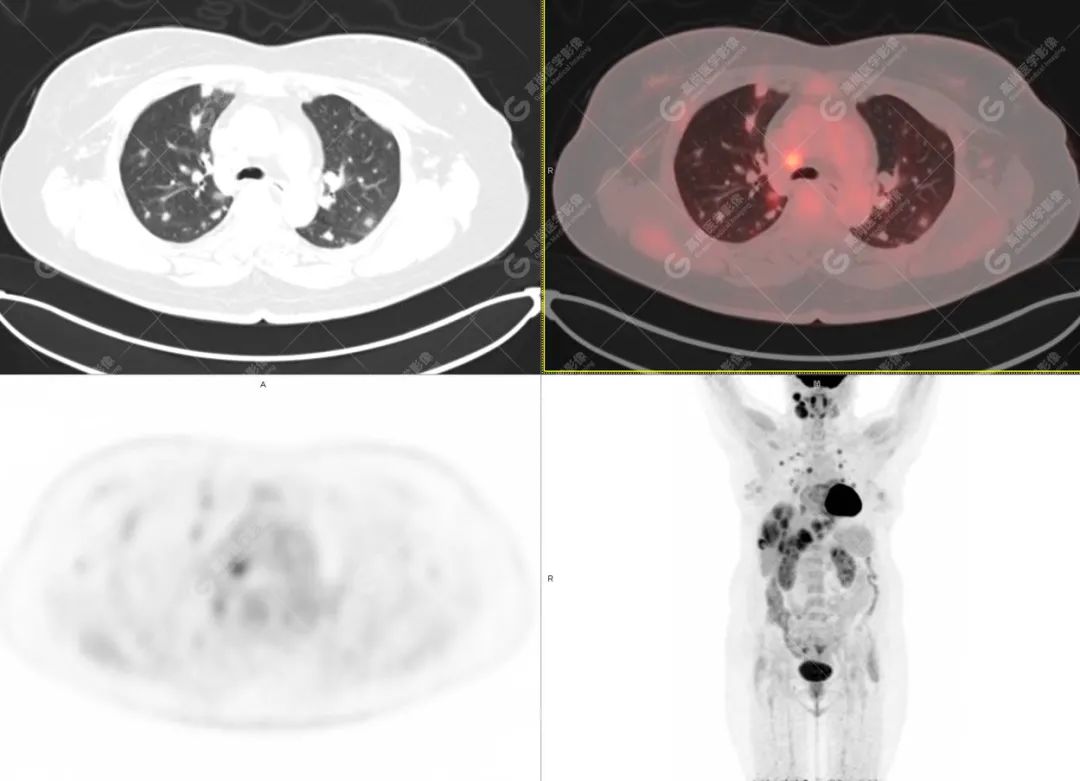

影像诊断:1. 结合病史,右颈部神经鞘瘤(低度恶性)术后改变,右侧颈部稍低密度及等密度结节,代谢异常增高,考虑为肿瘤复发并右颈部淋巴结转移,建议活检。 2. 双侧肺门及纵隔(4R 区)多发肿大淋巴结,代谢异常增高,考虑为转移。 3. 双肺多发大小不等实性结节,部分代谢增高,考虑为转移。 4. 肝脏多发低密度结节及肿块,代谢异常增高,考虑为转移。 5. 右侧第 8 前肋骨骨质破坏,代谢异常增高,考虑为转移。